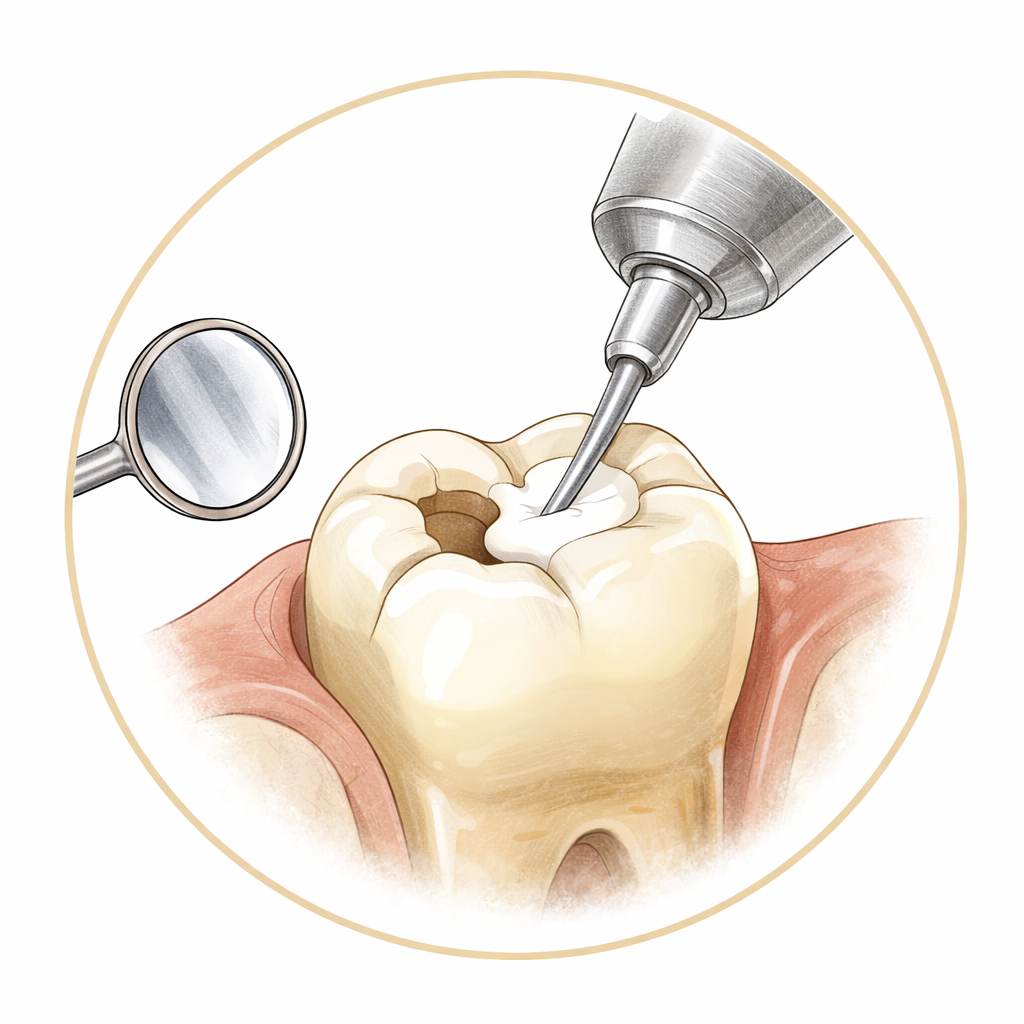

Dolgu, kanal tedavisi, diş çekimi, diş eti tedavisi ve koruyucu bakım — günlük diş sağlığınız için.

Tedaviler